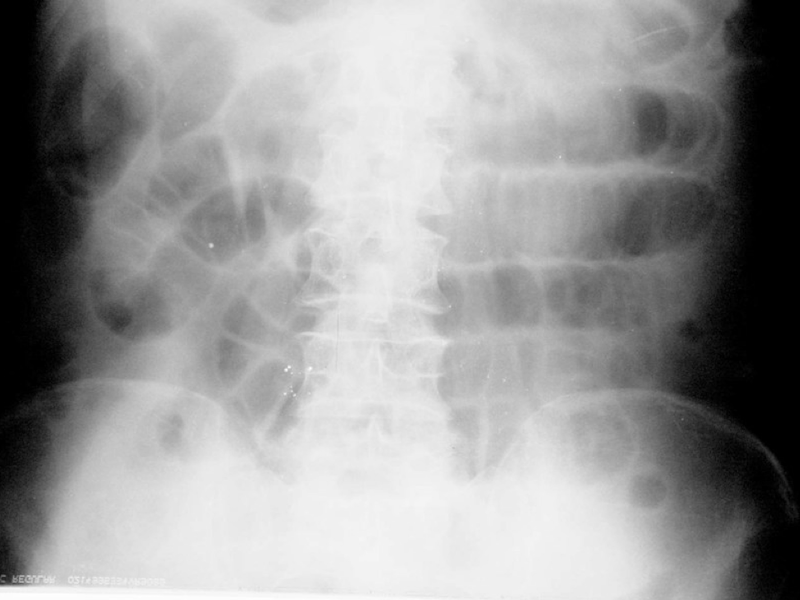

- Рентгенограмма брюшной полости: кроме жидкости и газа, можно увидеть признаки пареза кишечника (горизонтальные уровни жидкости в петлях кишечника со скоплениями газа над ними — так называемые Чаши Клойбера).